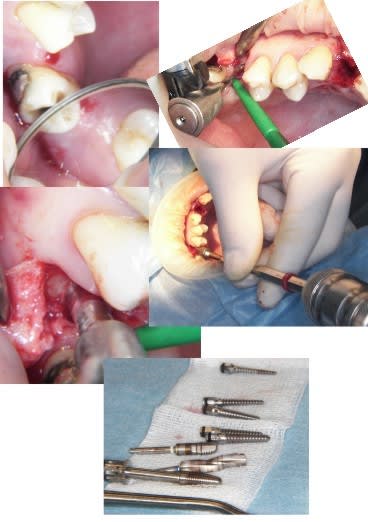

j'ai fait une bonne matinée implanto ce matin avec mélange des techniques 2 Summers avec un mélange expanseurs/condenseurs Meissinger, ostéotomes impactés pour la corticale qui faisait de la résistance, eponge pour la membrane, puis une reprise d'echec sur une mise en vitrine immédiate (fracture en mangeant une frite calcinée, à un mois!le 14/07)déposé le 15/07 mais avec mouvements pendant 24 heure et de 3.4mm j'ai du passer à 5.2!

les photos d'hier avec la mise en vitrine immediate et la reprise

--

xbk